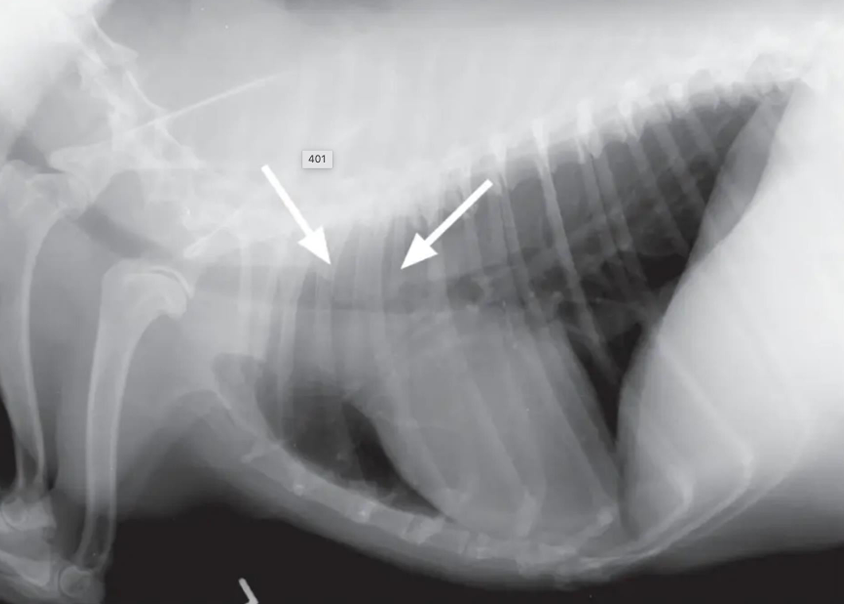

![]() | Pneumothorax - 폐가 쪼그라들면서 하얗게 보임 - 심장이 떠 있음 |

흉강에 공기가 차면서 폐가 쪼그라듦. → 심장이 위로 들림.

펼쳐진 폐가 쪼그라들면서 하얗게 보임.